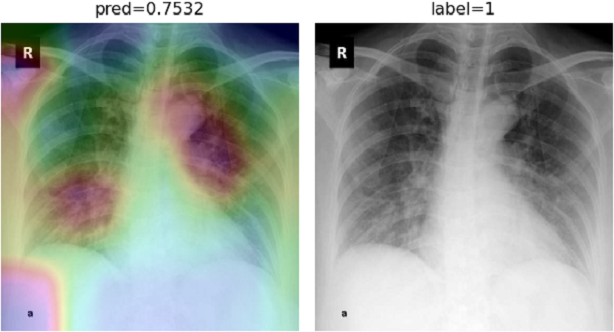

To overcome the aforementioned issues and force the model’s attention to the correct regions of interest (ROIs), we introduce the COVID-CXNet. Our model is initialized with the pretrained weights from CheXNet. A dataset of 3,628 images, 3,200 normal CXRs and 428 COVID-19 CXRs, are divided into 80% as training-set and 20% as test-set. Batch size is set to 16, rather than 32 in previous models, regarding memory constraints. Grad-CAMs of the COVID-CXNet for random images are plotted in Fig. 15.

Refer to caption

Figure 15: Grad-CAM visualization of the proposed model over sample cases

More Grad-CAMs are available in Appendix A. Heatmaps are more accurate than previous models, while an accuracy of 99.04% and an f-score of 0.96 are achieved. Table 3 is the confusion matrix of the proposed model.